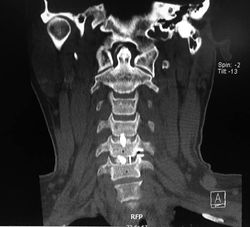

A 46-year-old patient with severe spastic tetraparesis, 6-month-old pyramidal syndrome, preoperative and post-surgical images after radical resection are shown posteriorly with resection of C3-C4 and C4-C5 facial complexes, posterior fixation with screws to lateral masses and sublaminar hooks, post operatively spinal reperfusion edema that determined severe left hemiparesis, with significant recovery 4/5 at 7 days post surgery. CSF fistula repaired in 2nd surgery 3 days after initial surgical act.